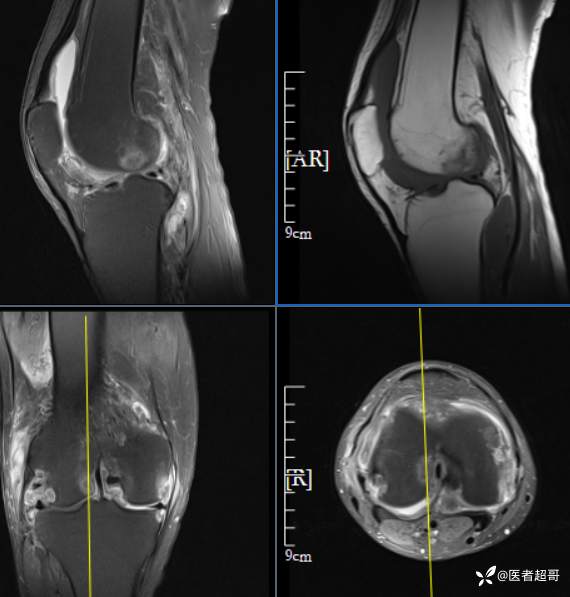

华夏览雄 等 2 位达人已点赞男性,55岁,右膝关节疼痛伴活动困难2年余

两年前外院行右膝包块切除术,术后病理为“肉芽肿”,具体不详,患者术后经常右膝关节积液,右膝活动困难,右膝疼痛明显

实验室检查:白细胞计数:9.0×10^9/L;葡萄糖(空腹):6.93mmol/L↑